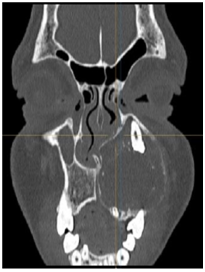

Panoramic Radiographic was obtained shows a large unilocular radiolucency on the left side of the maxilla, extending from tooth #22 to #26. Unerupted tooth #23 was present inside the lesion. Computed Tomography (Figure 2) (Figure 3) of facial bone was obtained shows well circumscribed unilocular radiolucency and radiolucency involves the crown of unerupted tooth #23. Based on the history and clinical features and radiographic evaluation dentigerous cyst and adenomatoid odontogenic tumour was made as provisional diagnosis. Other strictly radiolucent lesions worthy of consideration are keratocystic odontogenic tumor, ameloblastic fibroma, odontogenic myxoma, or central giant cell tumour as well as unicystic ameloblastoma which is common in this age.

Figure 2 Initial paranasal sinus computed tomography axial view.

Panoramic Radiograph does give a comprehensive view of the lesion, but a multi-slice CT scan provides the extension of the lesion in all directions besides showing dental involvement, as in this case it revealed intracapsular presence of canine tooth which couldn't hence be saved. It also showed involvement of the maxillary sinus and aided in treatment planning. Quality and quantity of the scattered radiopaque foci can also be well appreciated on the CT scan. CT scan provides proper extensions of the AOT, reveals proximity to the vital structures which aid in the preoperative evaluation, provisional diagnosis, planning and execution of the surgical procedure.